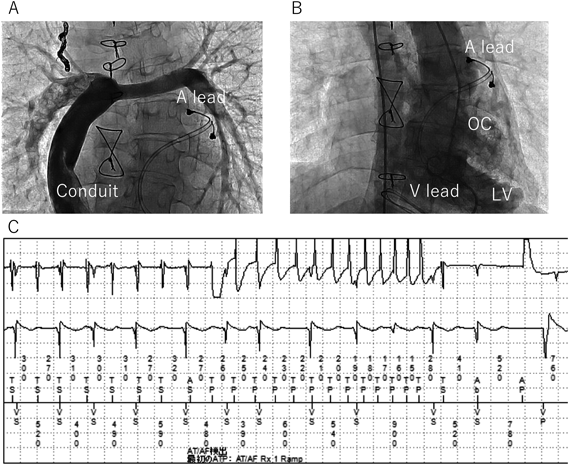

Fig. 5 Successful atrial anti-tachycardia pacing therapy for perioperative atrial tachycardia after Fontan conversion in a patient with single left ventricle

A: Venography in extracardiac conduit. B: Ventriculography. C: Atrial anti-tachycardia pacing (burst pacing) successfully terminated frequent perioperative atrial tachycardia. A, atrial; LV, left ventricle; OC, outlet chamber (rudimentary right ventricle); V, ventricle